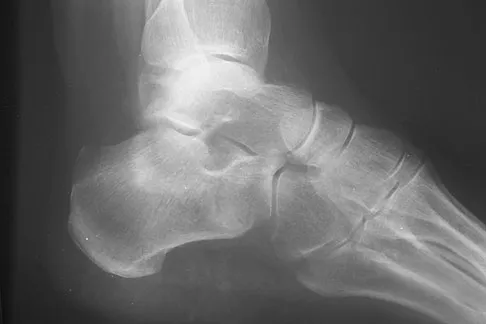

Question 78

Figures 48a and 48b show the radiographs of a 26-year-old woman who fell down two steps and twisted her foot and ankle. What is the most appropriate treatment for this injury?

Explanation

The patient has a zone 1 base of the fifth metatarsal fracture (Pseudojones) that represents a less serious injury compared to zone 2 and 3 fractures with regard to healing potential. Treatment is symptomatic and casting is not necessary. These fractures are well treated with a hard-soled shoe for comfort and weight bearing as tolerated. Surgical intervention is not warranted. Vorlat P, Achtergael W, Haentjens P: Predictors of outcome of non-displaced fractures of the base of the fifth metatarsal. Int Orthop 2007;31:5-10. Wiener BD, Linder JF, Giattini JF: Treatment of fractures of the fifth metatarsal: A prospective study. Foot Ankle Int 1997;18:267-269.